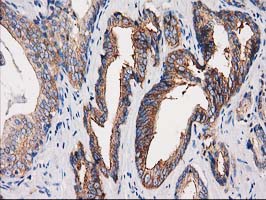

Immunohistochemistry analysis of paraffin-embedded Carcinoma of Human prostate tissue using PACSIN3 antibody.High-pressure and temperature Sodium Citrate pH 6.0 was used for antigen retrieval.